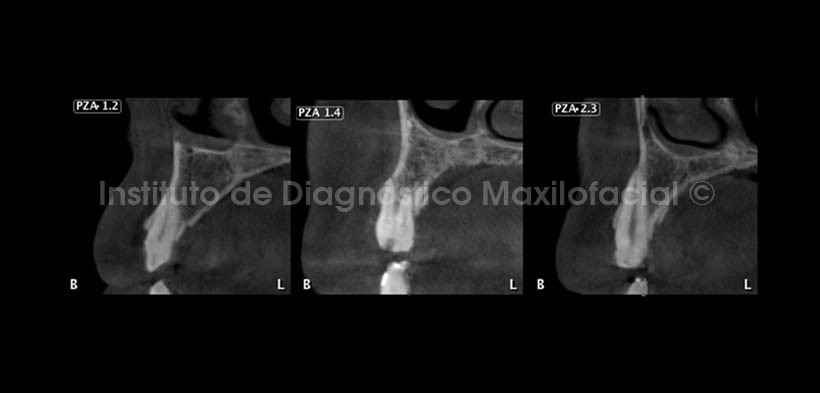

En cortes transaxiales (Fig.3 y 4) se observan diferentes piezas dentarias, notando el delgado grosor del esmalte en todas ellas, además se observan cavidades, las cuales pueden estar asociadas a este tipo de anomalía.